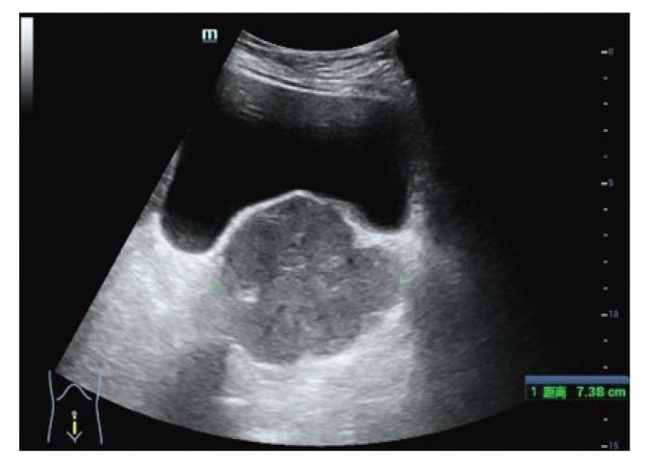

报告1例原发于宫颈的未分化子宫肉瘤病例。患者因绝经7年,阴道出血1周就诊,妇科检查触及宫颈9 cm大小的肿物,影像学检查提示宫颈巨大肿物及盆腔积液,未见明显肿大的淋巴结。遂行经腹全子宫切除术+双侧输卵管卵巢切除术,术后病理活检及免疫组织化学检查提示低级别未分化子宫肉瘤。术后患者拒绝放化疗,未定期复查。半年后再次因阴道出血,下腹部胀痛就诊,影像学提示阴道残端占位性病变,考虑肿瘤复发可能,遂行经导管髂内动脉栓塞术+髂动脉造影+动脉注射化疗药物(顺铂60 mg+表柔比星30 mg)。2个月后又因间断阴道出血在外院化疗1次。定期随访9个月,期间未行治疗,间断阴道出血。后失访。

A case of primary undifferentiated uterine sarcoma of the cervix is reported. The patient presented for medical consultation due to vaginal bleeding for 1 week after 7 years of menopause. A 9 cm mass in the cervix was detected during a gynecological examination. Imaging studies indicated a huge cervical mass and pelvic effusion, with no obvious enlarged lymph nodes. Subsequently, an abdominal total hysterectomy and bilateral salpingo-oophorectomy were performed. Postoperative pathological biopsy and immunohistochemistry suggested low-grade undifferentiated uterine sarcoma. After the operation, the patient refused radiotherapy and chemotherapy and did not undergo regular follow-up. Six months later, the patient presented again with vaginal bleeding and lower abdominal distension and pain. Imaging showed a space-occupying lesion at the vaginal stump, and tumor recurrence was considered possible. Therefore, transcatheter internal iliac artery embolization, iliac artery angiography and intra-arterial injection of chemotherapy drugs (cisplatin 60 mg + epirubicin 30 mg) were carried out. Two months later, the patient received chemotherapy once at another hospital due to intermittent vaginal bleeding. The patient was followed up regularly for 9 months, during which no treatment was administered, and intermittent vaginal bleeding occurred. The patient was then lost to follow-up.